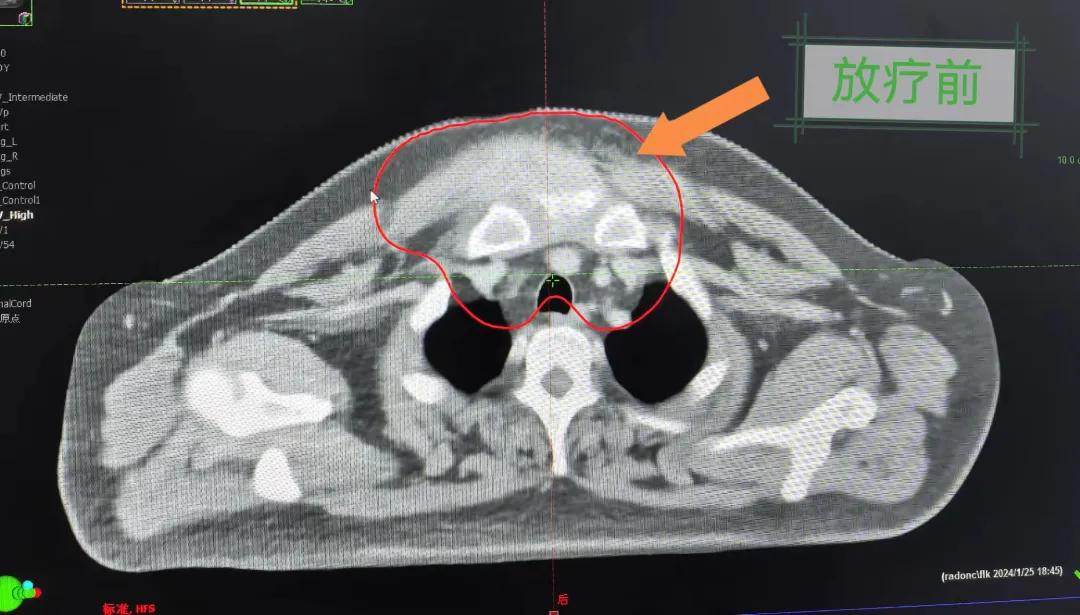

隨后,趙亮主任帶領放療團隊以最快的速度完成了患者的放射治療計劃,在保證放療精準打擊腫瘤的同時,利用先進的三維立體精確放療技術,最大限度的避免心臟、肺部的損傷發生,整體治療精準度達到1mm以內。經過10次的放射治療后,患者疼痛已明顯減輕,胸部腫物肉眼可見的縮小,患者及家屬臉上終于露出久違的笑臉。

治療期間,患者沒有出現明顯不適,治療結束后,患者胸壁腫物由最初8cm縮小至約1cm,后患者至外科行手術治療。